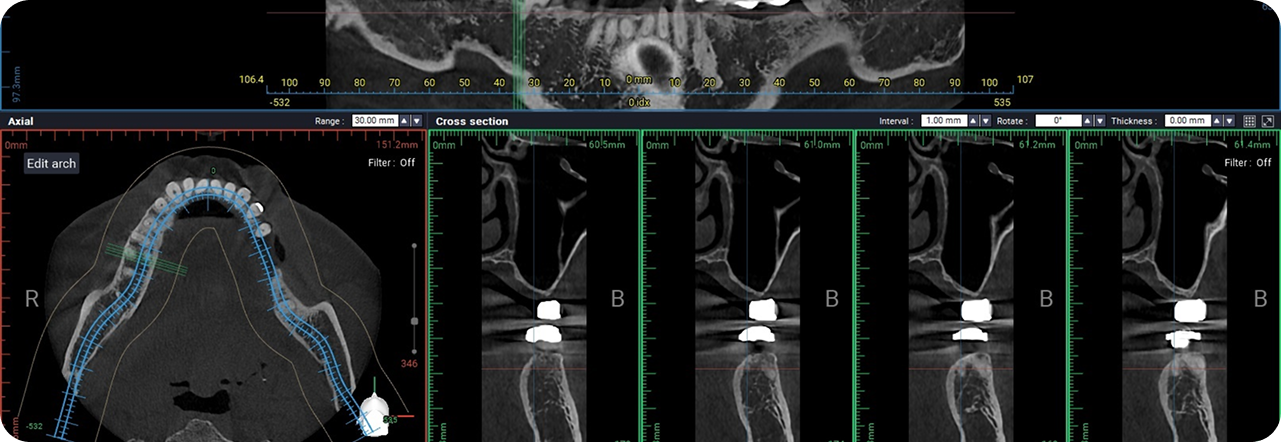

성공적인 임플란트 식립을 위해서는 정밀한 진단이 필수적입니다.

3D-CT, 구강 스캐너 등 다양한 디지털 장비를 이용하여

치아, 잇몸뼈, 신경 위치 등을 정확하게 파악해 수술 오차를 최소화하고,

통증 및 출혈을 줄여 더욱 안전하고 편안한 임플란트 식립이 가능합니다.

3D-CT를 통한 정밀 진단

3D-CT 분석을 통해 상악동 구조와

골 상태를 정확하게 진단합니다.